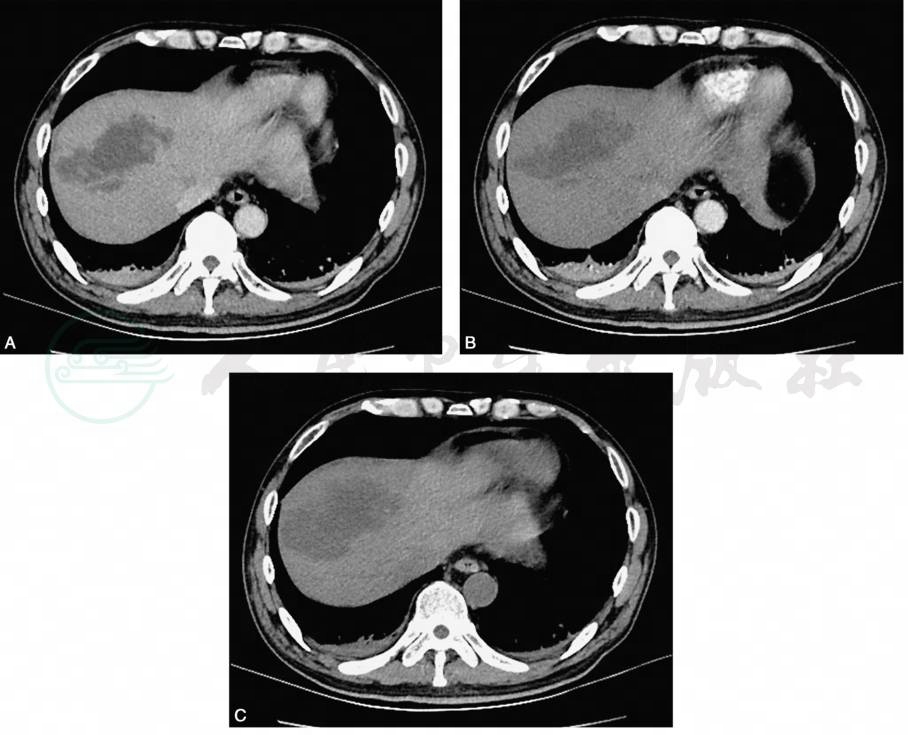

平扫病灶呈扇形、楔形或类圆形的片状低密度影,尖端指向肝门,边缘可较清晰锐利或略模糊,延伸至肝包膜,肝包膜累及的范围较大,部分病灶内可有更低气体密度影;增强后动脉期病灶无强化或边缘有环形或晕状强化,延迟期强化消失,呈等密度(图1)。

图1肝梗死肝叶型

引自:中华影像医学·肝胆胰脾卷.第3版.ISBN:978-7-117-28982-5.主编: